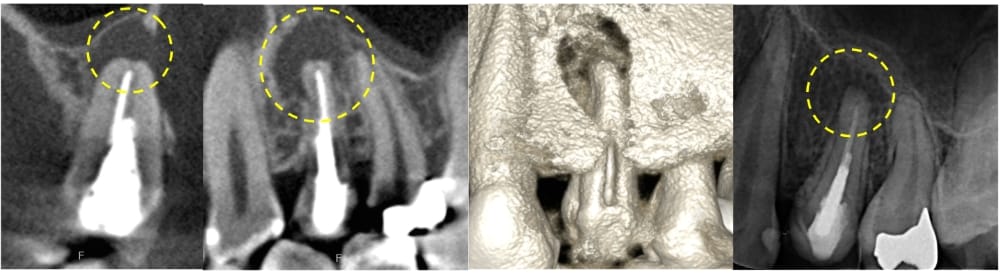

左上の第一小臼歯(4番)には虫歯が認められ、レントゲン・CTにて明瞭な骨吸収像が認められました。痛みなどの症状はないものの、このまま被せ物の治療をやりかえる場合、将来的に根の先の膿が大きくなる可能性があるため、根管治療が第一選択であるとお伝えし、根管治療を開始することになりました。

術後24ヶ月が経過時点でのCT画像では、もともとはっきりと写っていた根の先の黒い部分は完全に消失し、骨の回復が認められます。被せ物の適合にも問題なく、良好な経過をたどっています。